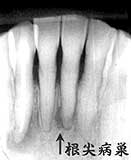

2| Dental写真 |1 Dental写真 同 口腔内写真

3年前には、2| 根尖に及ぶ歯槽骨吸収は認められない

66歳 男性

カリエスもなく根尖部から排膿

清掃状態はやや不良であるが、歯槽骨吸収は中程度で平均よりやや良好と思われた。問題の 下顎前歯部には、カリエスおよびカリエス治療の痕跡は見当たらない。

下顎前歯部については、1993年頃に知覚過敏症状を訴えているがその後は特に目立った症状 は認められなかった。その4年後('97)に2| の疼痛を訴えた時にはすでに歯髄壊死から比較的大きな根尖病巣に発展した状態であった。 そして今回('00)同様に、|1の歯髄壊死に よる症状を訴え根管処置を行ったが、'97年当時のレントゲンでもすでに歯髄壊死であったものと 推測される。

考察:

上行性歯髄炎は一般に“歯周疾患の進行が根尖部に及んだ結果、根尖部歯髄に炎症が波及し て歯髄を壊死せしめる”と解釈されているが、本性例においては、綿密なプロービングの結果根尖 に及ぶ歯槽骨の破壊は観察されていない。

上行性歯髄炎が歯周疾患の進行と深く関わっているであろうことは疑う余地のないことと思われ るが、“象牙質知覚過敏→歯髄炎→歯髄壊死→根尖病巣→エンド ペリオ”と考えるのが妥当だと思います。